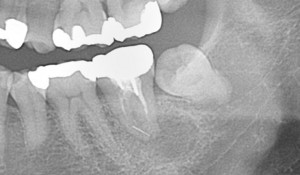

左下奥歯のレントゲン写真

レントゲンを見ると、確かに親知らずがあり、周囲に炎症が生じてもおかしくはない状況。

上記レントゲンにも、親知らずの一つ前の歯に病巣が確認できます。

赤い部分で囲った場所の骨が溶けてなくなっており、青い線の部分には、治療に使用するファイルが破折して残っています(破折ファイルについて詳しくはコチラ)。

かなり大きな病巣なので、もっと強い痛みが生じるはずでしたが、その歯を叩いても、硬いものを噛んでも痛みはないとの事。ただし、ふとした時に鈍痛が続くという症状でした。